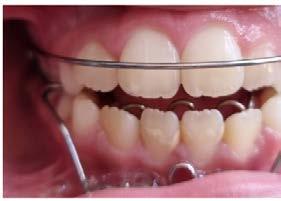

Se observó en la evaluación asimetría facial, tercio inferior aumentado, en la regla de quintos las líneas interpupilares no coinciden con la comisura labial, muestra 2/3 de las coronas superiores al sonreír y perfil retrusivo ocasionado por la distoclusión mandibular (Figura 1).

Su fonación no es clara, ya que presenta congestión nasal y hábito de lengua. Las fotografías intraorales de inicio se muestran en la Figura 2

Figura 2. Fotografias intraorales: A) fotografía de en oclusión, mordida abierta, línea media desviada. B) fotografía lateral, clase II subdivisión I.